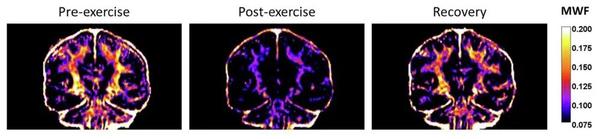

在一次马拉松比赛前48小时内,他们构建了10名受试者的脑髓鞘水含量(MWF)图谱。随后,他们在比赛后2天、2周和2个月后又分别测了受试者的脑髓鞘水含量。未比赛前,受试者大脑中的脑髓鞘含量大致相同,但在马拉松比赛后,他们的两个脑半球中的白质均出现了广泛的髓鞘丧失,且损失程度相当。

而这种损失涉及12个白质区域,包括脑桥交叉束、皮质脊髓束,以及前放射冠、后放射冠等。定量分析显示,脑桥交叉束、皮质脊髓束的MWF信号分别下降了28%和26%。这些区域主要参与运动功能的协调,以及大脑和小脑信息的整合。而前、后放射冠主要参与感觉情绪的整合。需要补充的是,MWF信号测的髓鞘减少,相比于真实的髓鞘减少——通过离体组织检测获得——通常会更多。所以真实的损害可能没有那么多。

另外值得庆幸的是,这种损失是可逆的,只是恢复得较慢。研究人员发现,比赛结束2周之后,这种损失部分恢复;而等到2个月时,则可以完全恢复。这似乎意味着,在大脑中,髓鞘就像一个储存能量的零钱包,在大脑缺乏营养物质时可以随时取用。

受试者大脑中的髓鞘在马拉松比赛前后的变化 图片来源于《自然·代谢》论文